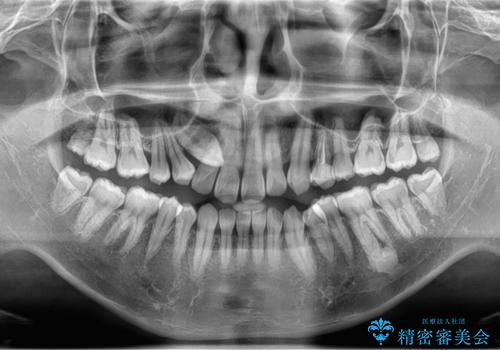

レントゲンを確認したところ上顎の犬歯が歯列不正により内側から生えてきたものでした。

抜歯をして欲しいとの依頼でしたのでCTを確認しながら抜歯術を行いました。